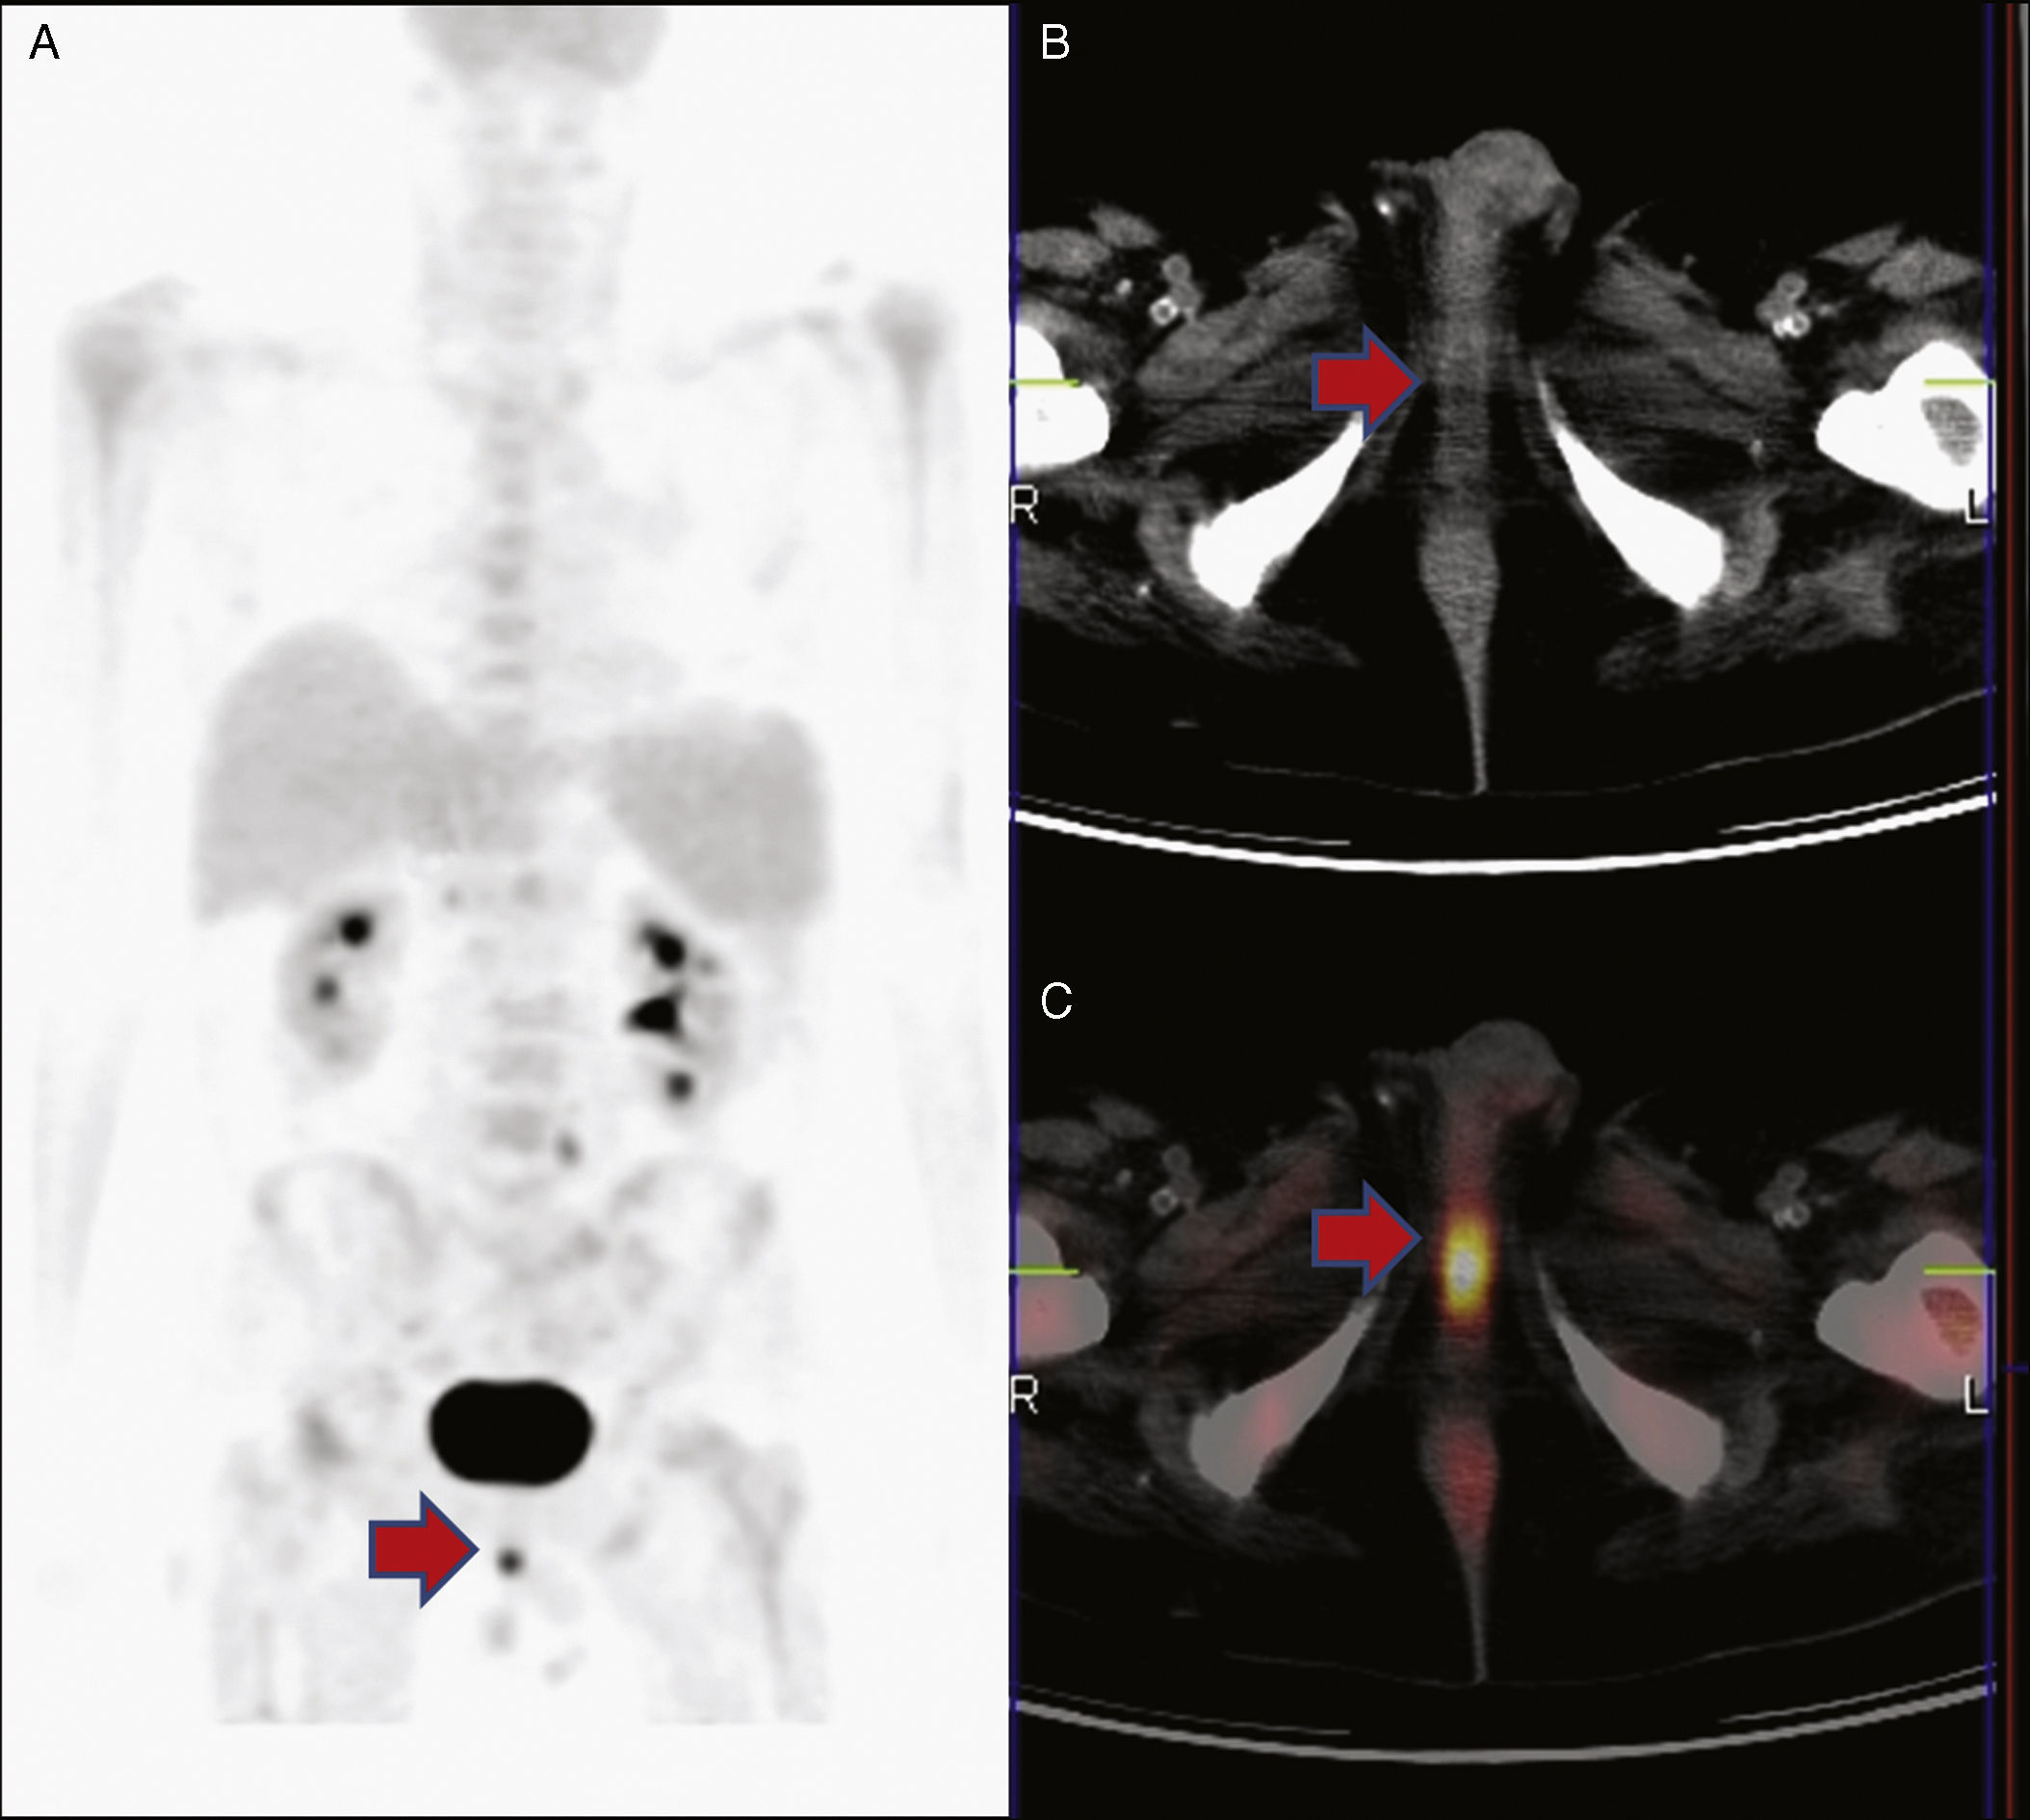

18F-FDG PET/CT detected a septic focus corresponding to a small periurethral abscess in a patient with bacteremia due to Enterococcus faecium

18F-FDG PET/TAC detectó un foco séptico debido a un pequeño absceso periuretral en un paciente con bacteriemia por Enterococcus faecium